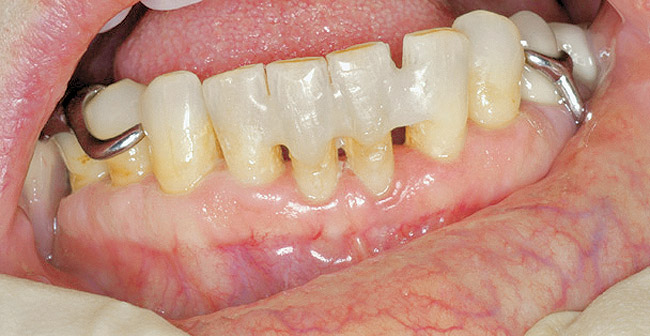

For patients on IV bisphosphonates, after bone is exposed, it is almost impossible to cover.15 Most cases worsen if surgical intervention is performed. Most patients must simply deal with the exposed bone and keep it clean so that bacterial infection does not occur. Figure 2 and Figure 3 show a postmetastatic prostate cancer patient with exposed bone. The treatment plan for this patient was to make a soft-lined denture that would not put pressure on the exposed bone and to check for bacterial infection on a routine basis.

Figure 2  Post-metastatic cancer patient with BRONJ in the lower right quadrant and in the lower left quadrant.

Figure 2

Figure 3  Post-metastatic cancer patient with BRONJ in the lower right quadrant and in the lower left quadrant.

Figure 3